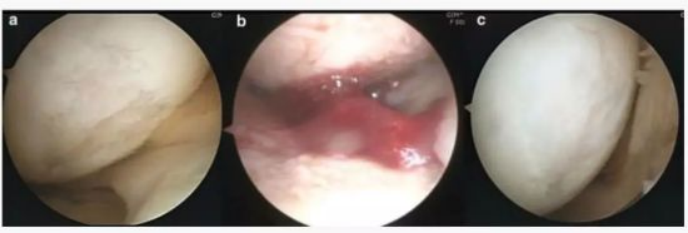

下图a为治疗前关节镜检查结果,,可以看出软骨存在缺损。。。。图b为脂肪间充质干细胞联合PRP治疗,,,图c为治疗后结果,,,通过间充质干细胞治疗,,,软骨得到了修复。。

下图可以看出从左往右随着间充质干细胞治疗的变化软骨逐渐得到修复